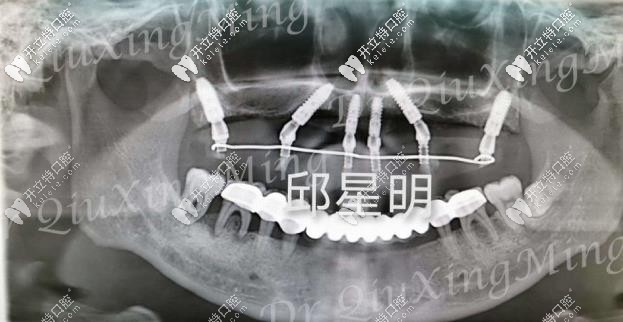

植入種植體的牙片

種植過(guò)程也挺快的,大約用了兩個(gè)多小時(shí),六根植體就已經(jīng)植入進(jìn)去了,然后需要等2-3個(gè)月的牙床恢復(fù)期,才能安裝基臺(tái)和牙冠。這段時(shí)間只需安心等待就好了!